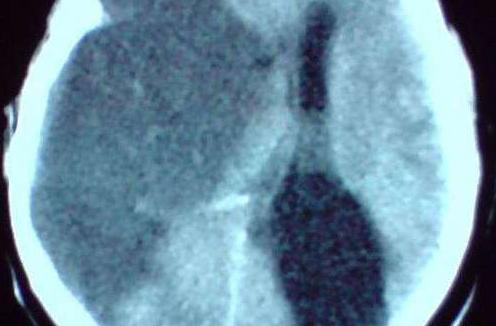

脑梗塞后遗症是老年人身上常见的疾病,对于每位脑梗塞后遗症患者来说,要是不想受到该疾病带给自己的伤害,就要及时的接受正规的治疗,以免影响了自己的病情,治疗脑梗塞后遗症时是有一些治疗原则的,有些患者经常会忽略,下面我们就来说说脑梗塞后遗症的治疗原则。